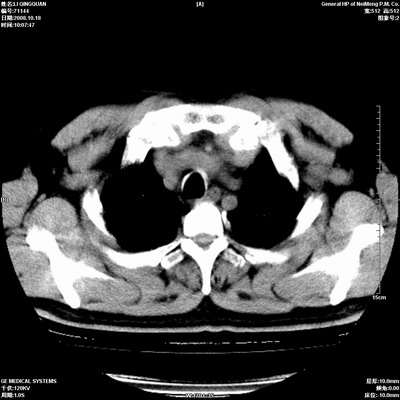

以下是引用duguo在2008-10-19 13:59:00的发言:[br]左肺上叶支气管狭窄,首先考虑中心型肺癌伴阻塞性肺炎\\肺不张.

以下是引用ybing在2008-10-19 12:58:00的发言:[br]左肺上叶阻塞性炎症-建议支气管镜进一步检查除外中央型肺癌

以下是引用随光逐影在2008-10-19 14:31:00的发言:[br]考虑左肺中央型肺癌并左肺上叶阻塞性肺炎,肺不张。